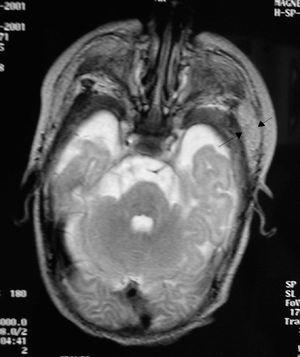

En el estudio ecográfico se observó aumento del tamaño de la glándula parótida con aumento de la vascularización que se confirmó en la resonancia magnética (RM) (fig. 2), descartándose la existencia de celulitis acompañante.

Figura 2. RM craneal del paciente 2. Se observa la glándula parótida izquierda aumentada de tamaño (flechas).

La analítica muestra signos de infección con aumento de reactantes de fase aguda. La amilasa en nuestros 2 pacientes fue normal, hecho descrito con frecuencia en la parotiditis supurativa neonatal, especialmente en la de origen bacteriémico. Para completar el diagnóstico se hace imprescindible el uso de pruebas de imagen como la ecografía, la tomografía computarizada (TC) o la RM, que demuestran un aumento del tamaño de la glándula parotídea unilateral con vascularización aumentada.